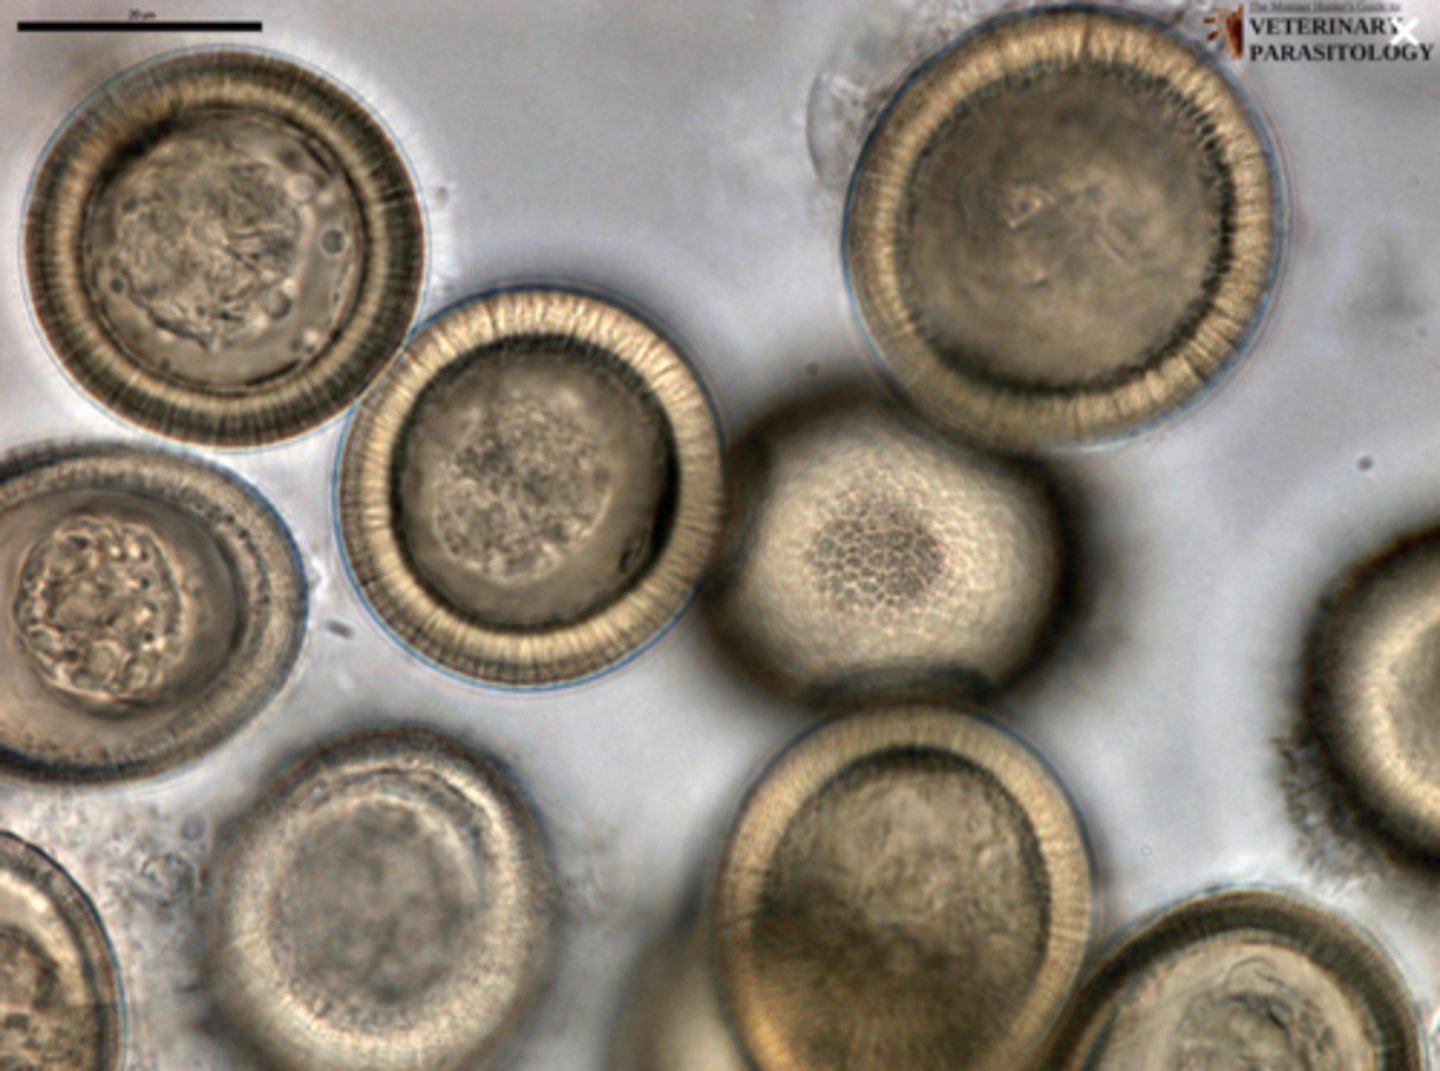

Taenia taeniaeformis (Tapeworm) (ova)

Which parasite is Ta if it is from a cat

Taenia pisiformis OR Echinococcus multilocularis OR Echinococcus granulosus (Tapeworm) (ova)

What parasite is this if it is from a dog

What parasite is this if it is from a cat